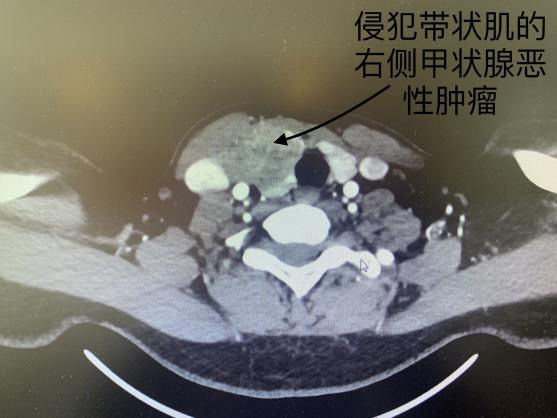

据悉,患者为34岁女性,因颈部多发肿物就诊于我院肿瘤科。经过详细的术前检查,发现患者右侧甲状腺肿物高度怀疑为恶性,且肿瘤巨大、边界不清,与周围组织广泛粘连,同时合并右颈部多发淋巴结肿大,考虑淋巴结多发转移。

面对这一病情,科室主任李庭军带领肿瘤外科组进行了周密的术前讨论,制定了详尽的手术计划和准备。手术过程中,经冰冻切片检查,证实了患者右侧甲状腺肿瘤的恶性性质,肿瘤科团队果断决定为患者实施“甲状腺癌根治术+右侧功能性颈淋巴结清扫术”。经过几个小时的努力,手术顺利完成。